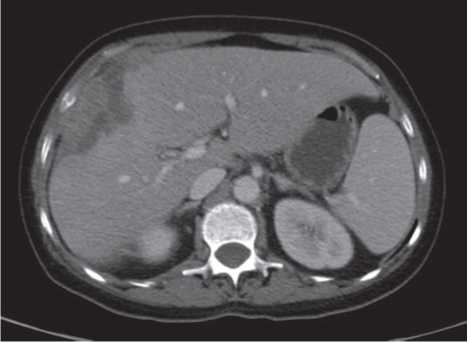

На начало терапии имелся сливной таргетный очаг в печени с преимущественным поражением правой доли – 203 мм, нетаргетные очаги – метастазы в легкие до 5 мм, свободная жидкость в брюшной полости в незначительном количестве (рис. 3, 4).

Рис. 4. КТ ОБП, венозная фаза. Сумма наибольших диаметров таргетных очагов 203 мм.

Fig. 4. Venous phase abdominal CT. The sum of the longest diameter of the target lesions is 203 mm.